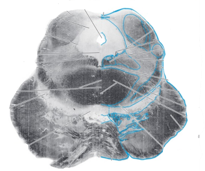

Q

Name this brainstem cross section:

A

Rostral midbrain